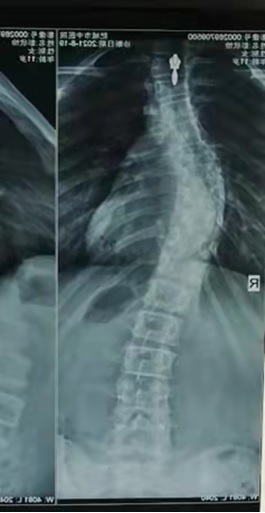

侧弯患者矫正案例

2021年8月患者初诊侧弯T9侧弯cobb43°,适配SCH侧弯支具后T9侧弯减至cobb20°,效果明显。